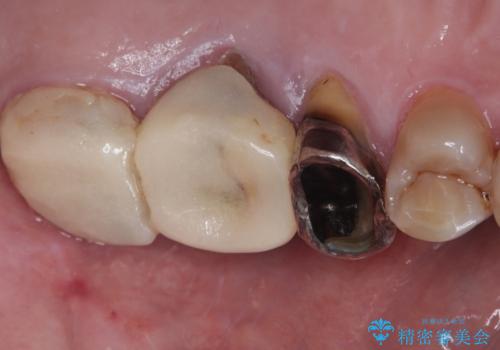

- 左下奥歯のインプラント治療と左上の被せもののやり替えを希望されて来院された患者様です。

左上の奥2本は他院で根管治療と仮歯まで入れている状態です。根管治療のやり替えは希望されなかったため被せものから治療していくことにしました。

その手前の小臼歯は根尖病変が認められるため根管治療のやり直しからしていくこととしました。